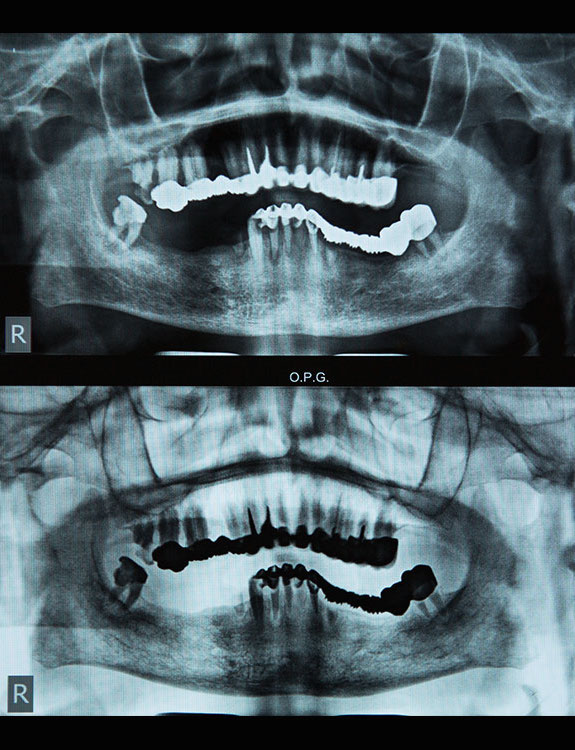

Missing teeth can affect not just your smile, but also your confidence, chewing ability, and overall oral health. At Dental Que, we offer advanced Dental Implants in Punjabi Bagh, West Delhi, designed to restore the look, feel, and function of natural teeth with long-lasting results.

Dental implants are artificial tooth roots made of medical-grade titanium that are surgically placed into the jawbone. Once the implant integrates with the bone, a crown is fixed on top, giving you a strong, natural-looking replacement tooth.